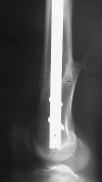

Attached are few examples from our Hospital:

A. Difficult reductions, even in retrograde nailing (my preference, easier control of "small" distal fragment) and it is much, much harder to do it anterograde (Alex, do you have one good case in your collection of anterograde nailing in very distal fractures - as you have suggested that I

should have done it in my previously posted case?

Malpositioning is much too common (recurvatum, varus - valgus).

B. Fixation loosening: distal cutting of the nail, non-unions do happen (cases attached).